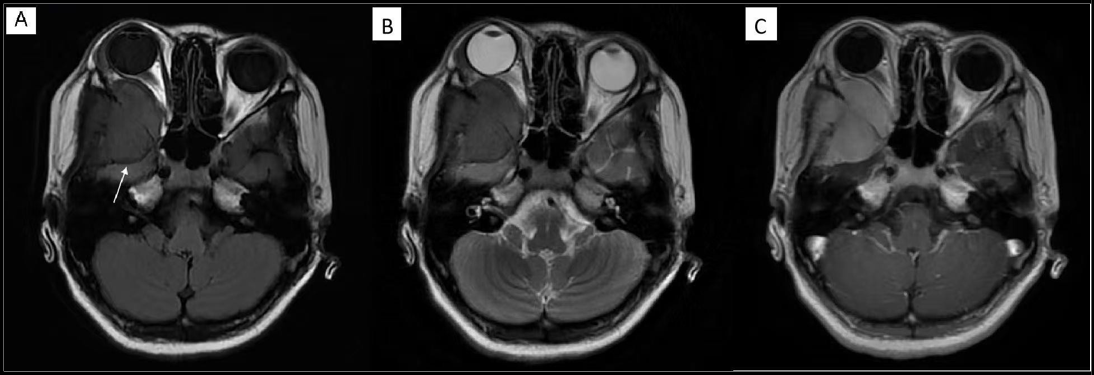

A rare case of isolated intracranial MS with PML:RARα fusion was identified in a 15-year-old female who presented with a 2-week history of persistent headache and swelling of the right cheek. Magnetic resonance imaging revealed a 4.7 × 4.6 × 4.8 cm mass in the right temporal region (Figure 1). Neuronavigation-guided craniotomy was performed to achieve surgical resection. Histopathological evaluation demonstrated a small, round-cell malignant neoplasm with areas of necrosis. Immunohistochemical (IHC) staining of core biopsy material showed that immature myeloid cells were positive for myeloperoxidase and Ki-67 (15%) and negative for CD34, CD30, CD68, CD138, CD20, and CD163. DNA-based targeted next-generation sequencing of the resected tissue confirmed the presence of PML:RARα fusion with a positive rate of 44.57%. Fluorescence in situ hybridization demonstrated 82% positivity for the same fusion (Figure 2). Peripheral blood counts, coagulation parameters, bone marrow examination, and cerebrospinal fluid (CSF) analysis were unremarkable, establishing the diagnosis of isolated intracranial MS with PML:RARα fusion.

Figure 1: Magnetic Resonance Imaging (MRI) Of The Brain.

A: T1-weighted MRI showing an isointense lesion (mass) in the right middle cranial fossa, involving adjacent meninges and temporal bone (white arrow).

B: T2-weighted MRI showing low signal intensity of the lesion.

C: Contrast-enhanced MRI showing marked enhancement of the lesion (mass).